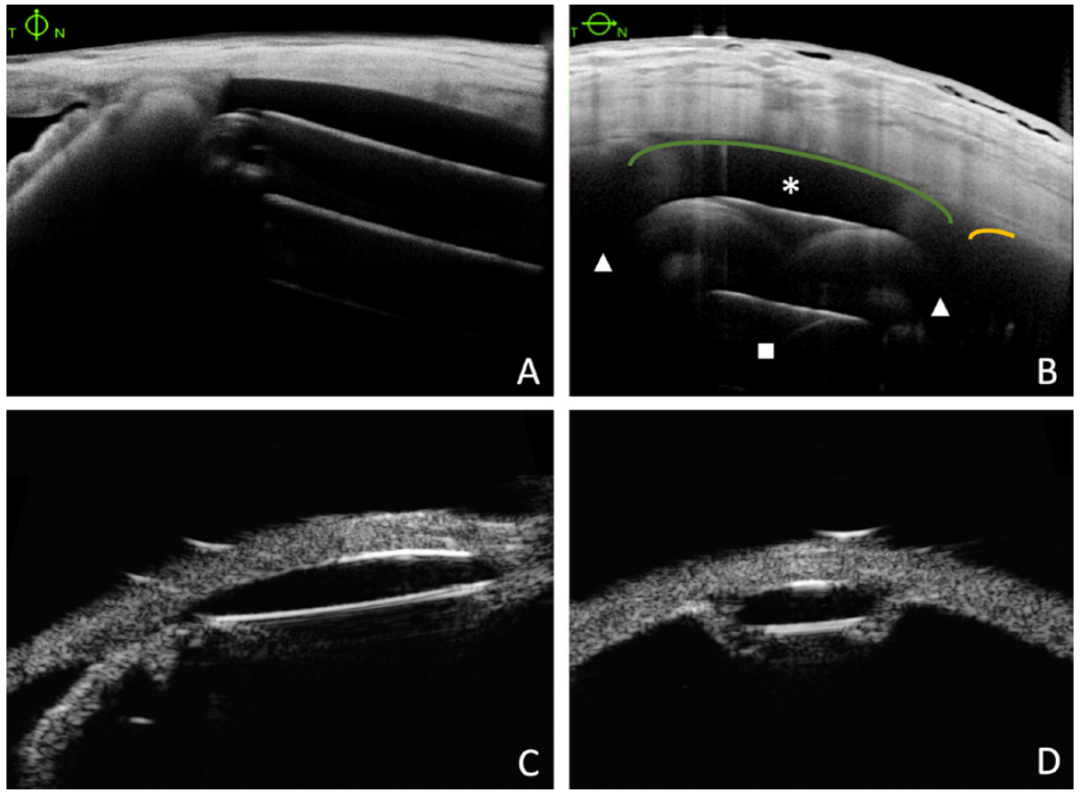

芯片的构造如上图的A、B所示。芯片内含压力与温度传感器,并连接一线圈,以医用级硅胶材料完全密封。其大小为7.5×3.5毫米,中心为1.3毫米厚度,向外递减到外围为0.9毫米。其表面弯曲弧度与巩膜相似,以适应生理形状。芯片中金属全部为金和铝,完全无磁性,已通过MRI安全性测试。

且通过前节OCT及UBM检查该设备植入后的位置、朝向及其与巩膜突的相对距离,结果显示其植入具有良好的空间稳定性。此外,未有植入后发生永久性设备故障的报告。